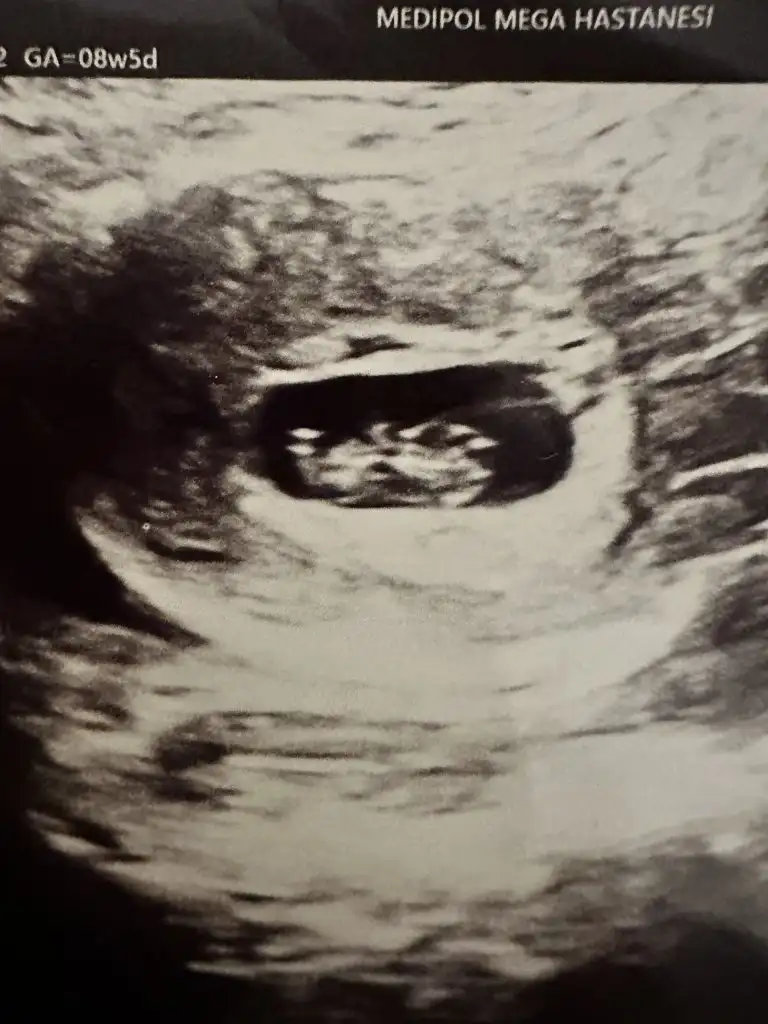

Merhaba rica etsem bizede bir tahmin yapar mısınız?Rica ederim canım ne demek biz sadece tahminde bulunuyoruz. Anne ne hissederse genelde o olur diyorlar belki sen dogruyu hissediyorsundur canım saglıkla gelsin inşallah![]()

Canım kız bebek gibi ama tam emin olamadımMerhaba rica etsem bizede bir tahmin yapar mısınız?![]()

Gözün aydın canım saglıkşa kucagına al inşallah ben bu haftalarda pek anlamıyorum kuzum işk haftalar plesentasına göre yorumluyorum. Bebegi ilk gördügün haftalar var mı erkek demiş bakim dogru çıkıyor mu olesentya göre merak ettim rica etsem atarmısın ilk haftalarŞimdi kontrolden çıktım %95 erkek %5 yanılma payı bırakıyorum dedi doktor canım oda çok düşük ihtimalTeşekkür ederim

Erkek bebekmiş canım saglıkla gelsin inşallahHemen atıyorum bir tane oğlum var ne yalan söyleyim bunu en başından beri kız hissediyordum sağlıklı olsun tabi o önemli ama onuda tatmak istiyor insan 8+5 ve 10 haftalık bunlar